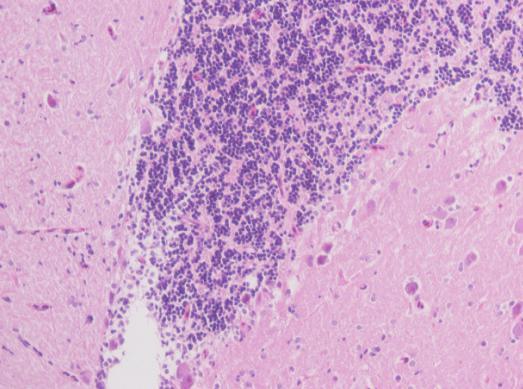

rt,做了脑组织的he染色,实验室以前从来没有人做过,拍出来的片完全不会分析啊,哪位大侠帮助在照片上对片中所拍摄到的正常结构和出现损伤的部位标示下啊,不胜感激啊,满意了会增加金币的 456.JPG 789.JPG 123.JPG |